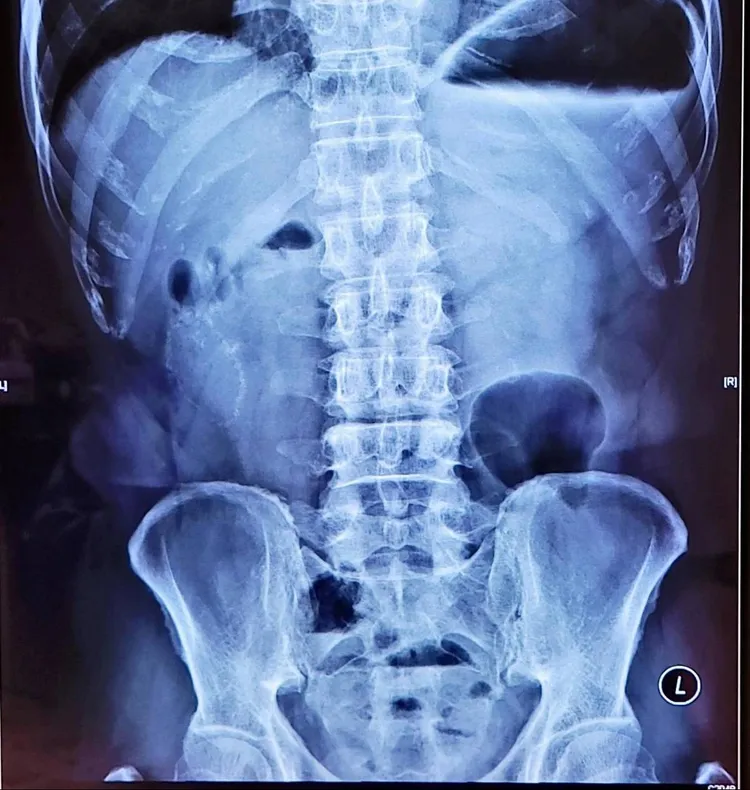

高雄這名大叔曾因腸子壞死部分切除,吃肉粽後腹痛住院六天。院方提供

阮綜合內科醫師蕭偉成也說,原本就有胃食道逆流、胃潰瘍、胃發炎、便秘等病史的民眾,逢端午常併發「舊疾復發」。近日就有一名曾因小腸缺血壞死接受部份切除的53歲男子,兩天內吃了3顆肉粽,導致腹脹嘔吐而住院,經過鼻胃管引流與藥物、輸液治療,六天後順利出院。